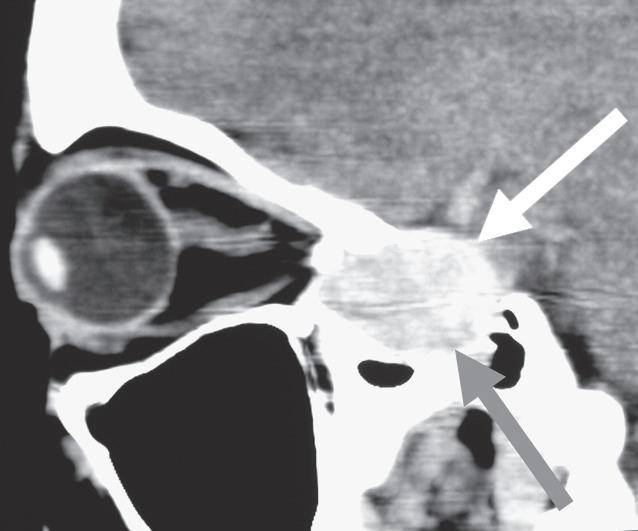

1.4 Not all acute optic neuropathies in young adults are optic neuritis! A This 32-yearold woman presented with progressive visual loss in the right eye over 3 weeks (right 20/60), pain behind the right eye, a right RAPD and normal optic discs. Her ophthalmologist diagnosed “retrobulbar optic neuritis” and reassured the patient that her vision would return spontaneously. Three months later, vision had worsened (20/200) and optic atrophy had developed; B MRI showed this large nasal tumor compressing the right optic nerve. Vision did not improve after removal of the tumor. Visual outcome would probably have been better with earlier diagnosis. For how to safely diagnose typical optic neuritis, see p. 35.

1.4

Not all acute optic neuropathies with a swollen disc are AION! This 55-year-old hypertensive man complained of progressive loss of vision in his right eye over 7 days. His ophthalmologist found C right visual acuity to be 20/40, a right RAPD and right optic disc swelling. A right inferior altitudinal scotoma was detected on perimetry. The ophthalmologist diagnosed “anterior ischemic optic neuropathy” and advised the patient that there was no treatment. Ten weeks later, right visual acuity (VA) had deteriorated to 20/400 and the right disc had become pale; further investigation revealed an increased serum angiotensin converting enzyme (ACE) and D hilar lymphadenopathy on chest x-ray. Biopsy of a lower eyelid conjunctival granuloma confirmed the diagnosis of sarcoidosis. Because diagnosis was delayed, right VA only returned to 20/80 with steroid treatment. For how to safely diagnose AION, see p. 36.

D